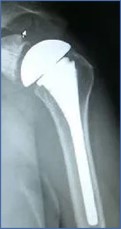

Shoulder Joint implants

Shoulder Specification

ASTM F1378: Standard Specification for Shoulder Prostheses.

Shoulder Implant Requirements

ISO 21534:Non-active Surgical Implants- Joint replacement

Implants- Particular Requirements.